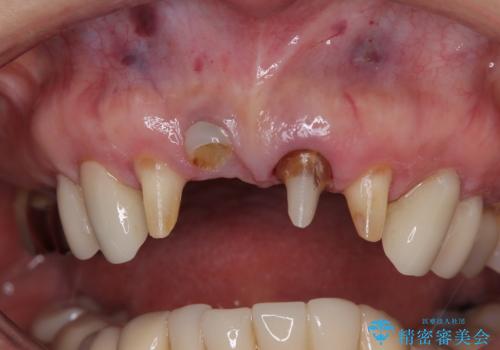

- 歯肉ラインの段差や、歯根が黒く見えている前歯を気にして来院された患者様です。

前歯のインプラントは埋入されたポジションが望ましい位置ではなく、インプラントを活用して段差を回収することは不可能と判断し、歯肉移植によりインプラントを隠して、ブリッジにて歯肉ラインを整えることとしました。

臼歯部の治療も必要と判断されましたが、前歯部を中心とした審美領域をオールセラミッククラウンによる補綴治療を行うこととしました。